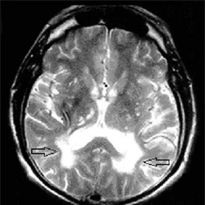

Înainte de apariția de dispozitive de diagnosticare, oferind vizualizarea zonelor cu o densitate scăzută a materiei albe despre leykoareoz ca un fenomen separat, nimeni nu a vorbit. Acum, modificările patologice ale structurilor subcorticale determinate cu succes pe RMN-ul care dezvăluie leykoareoz prima etapă și productivă amâna debutul celei de a doua.

Cea mai eficientă metodă este de a determina modul de leucoaraioză IRM T2 EV (imagine ponderată).

Leucoaraioză focare in creier se poate manifesta prin CT (tomografie computerizata), dar eficiența acestei metode în diagnosticul unei patologii într-o primă etapă în procedura de mai jos.